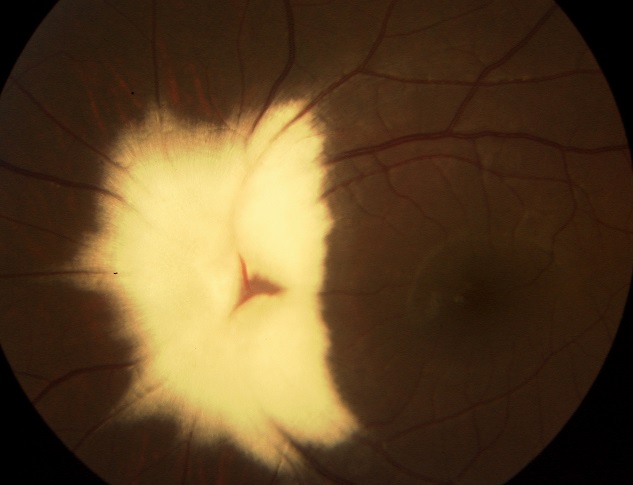

Myelinated retinal nerve fibers

A 7-year-old girl of second degree consanguineous parents, presented with an 8 months history of intermittent exotropia of the left eye. Cycloplegic refraction was -0.25.-0.50×165º and -3.00.-0.50×20º in the right and left eyes respectively. An initial objective assessment of the visual function showed a best corrected visual acuity of 12/10 in the right eye and 6/10 in the left eye. Fundoscopy revealed superficial whitish, opaque lesion with feathered edges, hiding the optic disc and retinal vessels, and following the course of the nerve fiber layer in the left eye. We conclude to the diagnosis of myelinated retinal nerve fibers. General examination was unremarkable. The treatment of amblyopia was then undertaken, and a final corrected visual acuity of 9/10 was attained in the left eye. Myelinated retinal nerve fibers are a rare idiopathic developmental abnormality, occurring when the myelination of ganglions cells axons extend abnormally into the retina. Usually, this malformation does not affect visual acuity, unless it involves the fovea. Otherwise it can be, rarely, associated with myopia, strabismus, and amblyopia. Amblyopia treatment should be systematically considered, even if it’s reported to be refractory to the treatment in such cases.General clinical assessment must be carried out in order to exclude some systemic disorders that may be linked to this abnormality including neurofibromatosis type 1, craniofacial abnormalities, skeletal malformations, and basal cell nevus syndrome.